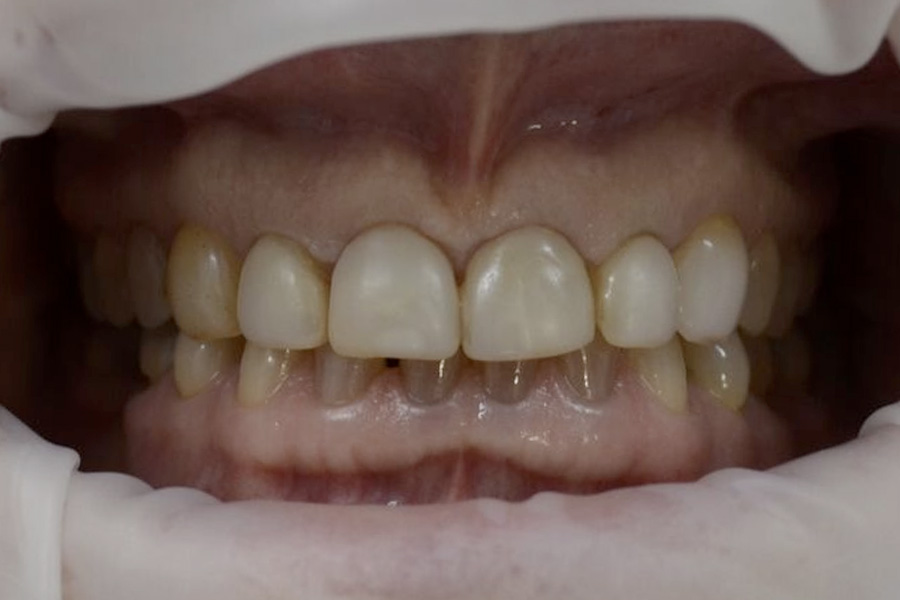

Brooke had a single crown on the upper left central incisor that had a receding gum line.

Some of the white fillings on other front teeth were also stained. Deb decided to have the crown replaced and ceramic veneers placed on other teeth. The new crown on the upper left central incisor is all ceramic (without any metal on the inside) and blends in more naturally with the veneers.